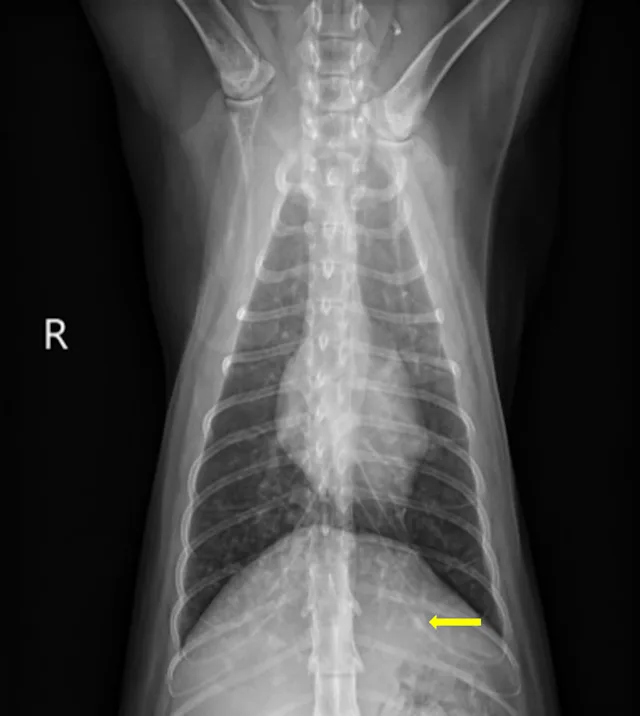

At the 1-month recheck, her weight had increased to 6 lb (3 kg); estimated BCS was 3/9. Physical examination showed a normal respiratory pattern, but increased bronchovesicular sounds were still present bilaterally. No fundic abnormalities were noted. Radiographs indicated subtle improvement of the diffuse nodular pulmonary pattern (Figure 2).

A

FIGURE 2 Left lateral (A), right lateral (B), and ventrodorsal (C) thoracic radiographs 1 month after initiation of itraconazole. Subtle improvement of the diffuse nodular pulmonary pattern can be seen.